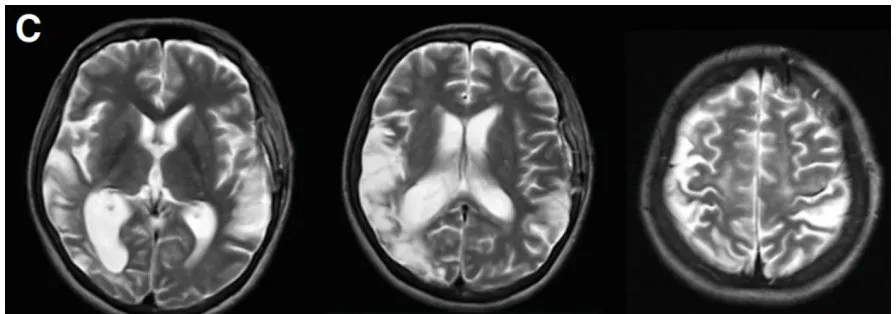

1个月后,幸子因构音障碍和右腿无力入院,并在左额叶出现新的脑梗死(图1C)。随后出现甲状腺风暴(fT4 3.91 ng/ml,fT3 10.09 pg/ml)——甲状腺机能亢进的合并症,是一种少见但能致死的病症。伴有发热、心动过速和高血压等甲状腺毒症症状。

▼C,术前T2、DWI序列显示左额叶新发展的脑梗死。

▼D,入院3天后术前T2、DWI序列显示左侧颞叶进一步新发脑梗死